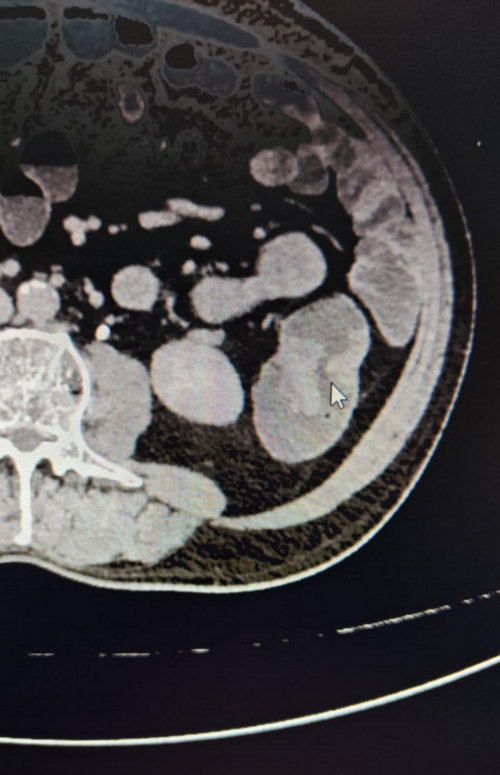

Case Summary Case Title: Chronic Calcific Pancreatitis Surgery Performed: Frey’s Procedure (Pancreatic Head Resection with Lateral Pancreaticoj...